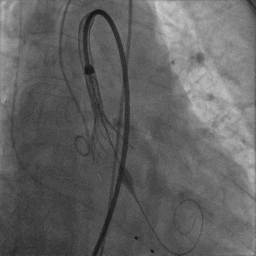

首次释放时,受自身瓣叶挤压,人工瓣膜略有下滑,造影后有轻中度瓣周漏,后对人工瓣膜进行回收。

部分回收后,对人工瓣膜重新定位并释放,位置理想且基本与瓣环齐平。